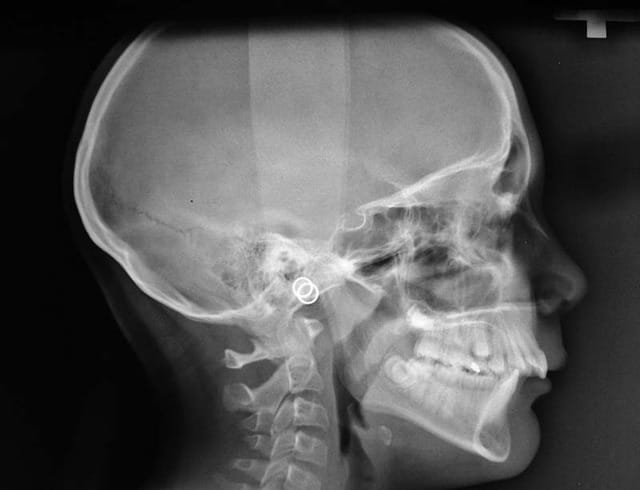

25/06/2009 à 13h57

complément Rx. demandés

@+ Bjc.